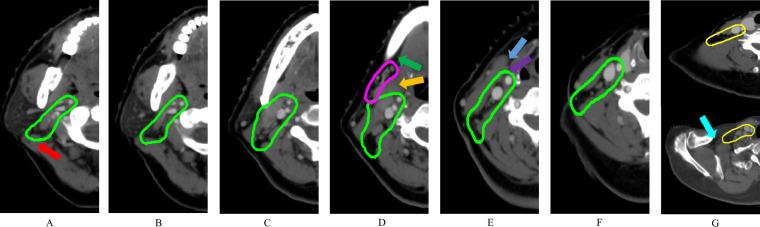

The deep learning (DL)-based prediction of accurate lymph node (LN) clinical target volumes (CTVs) for nasopharyngeal carcinoma (NPC) radiotherapy (RT) remains challenging. One of the main reasons is the variability of contours despite standardization processes by expert guidelines in combination with scarce data sharing in the community. Therefore, we retrospectively generated a 262-subjects dataset from four centers to develop the DL models for LN CTVs delineation. This dataset included 440 computed tomography images from different scanning phases, disease stages and treatment strategies. Three clinical expert boards, each comprising two experts (totalling six experts), manually delineated six basic LN CTVs on separate cohorts as the ground truth according to LN involvement and clinical requirements. Several state-of-the-art segmentation algorithms were evaluated on this benchmark, showing promising results for LN CTV segmentation. In conclusion, this work built a multicenter LN CTV segmentation dataset, which may be the first dataset for automatic LN CTV delineation development and evaluation, serving as a benchmark for future research.

深度学习(DL)在预测鼻咽癌(NPC)放疗的准确淋巴结(LN)临床靶区(CTV)方面仍然具有挑战性。其中一个主要原因是,尽管有专家指南的标准化流程以及社区内数据共享的缺乏,但轮廓的可变性仍然存在。因此,我们从四个中心回顾性地生成了一个包含 262 个病例的数据集,用于开发 LNCTV 勾画的 DL 模型。该数据集包括来自不同扫描阶段、疾病阶段和治疗策略的 440 张 CT 图像。三个临床专家委员会,每个委员会由两名专家组成(共计 6 名专家),根据 LN 的受累情况和临床要求,在单独的队列上对六个基本 LNCTV 进行了手动勾画,作为金标准。在这个基准上评估了几种最先进的分割算法,它们在 LNCTV 分割方面显示出了很有前景的结果。总之,这项工作构建了一个多中心的 LNCTV 分割数据集,这可能是第一个用于自动 LNCTV 勾画开发和评估的数据集,可为未来的研究提供基准。